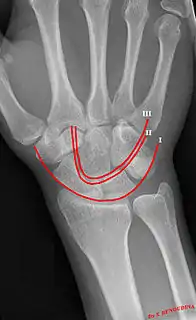

Gilula's lines

Gilula's lines are three arcs drawn on an AP radiograph of the wrist used to assess the alignment of the carpal bones.[1]

Gilula carpal arcs.

There should be no step-off in the contour of the lines when drawn on a normie wrist.

| First arc | running along the proximal convexity of the scaphoid, lunate and triquetrum |

| Second arc | running along the distal concavities of the scaphoid, lunate and triquetrum |

| Third arc | running along the proximal curvatures of the capitate and hamate |